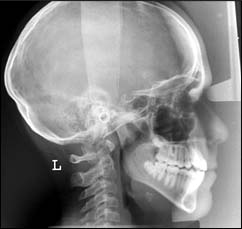

TÉLÉRADIOGRAPHIE DE PROFIL ET DE FACE :

Ces examens sont principalement réalisés dans le cadre d’un traitement ODF ; ils ont pour but de permettre un diagnostic et un pronostic précis pour entreprendre un traitement.